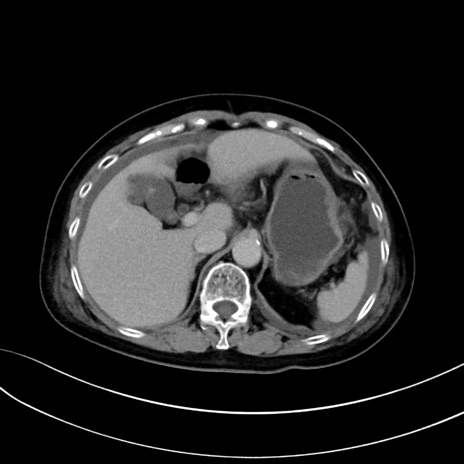

症例13 CT(横断像)1日半後